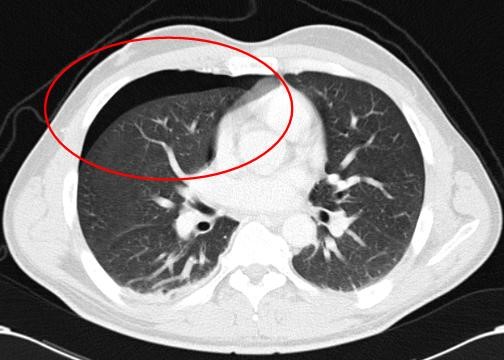

CT scan van de borstholte met daarop een (kleine) klaplong

Klaplong of bloed tussen de longbladen: wanneer er bij een klaplong (= ‘pneumothorax’) slechts een beetje lucht tussen de longbladen zit of wanneer er slechts een beetje bloed tussen de longbladen zit (‘hematothorax’) en de long dus maar weinig ingeklapt is en de patiënt hierbij niet benauwd is, kan dat afwachtend worden behandeld en dient de patiënt over het algemeen goed in de gaten te worden gehouden. Wanneer de hoeveelheid lucht groter is (en de klaplong dus ernstiger) of de hoeveelheid bloed tussen de longbladen groter is, dan zal er operatief een slang (zogenaamde ‘thoraxdrain’) tussen de longbladen moeten worden geplaatst, zodat de lucht of het bloed er tussenuit kan en de long zich weer goed kan ontplooien. Deze drain kan afhankelijk van het beloop meestal na enkele dagen er weer uit worden gehaald als de long weer helemaal ontplooit is.